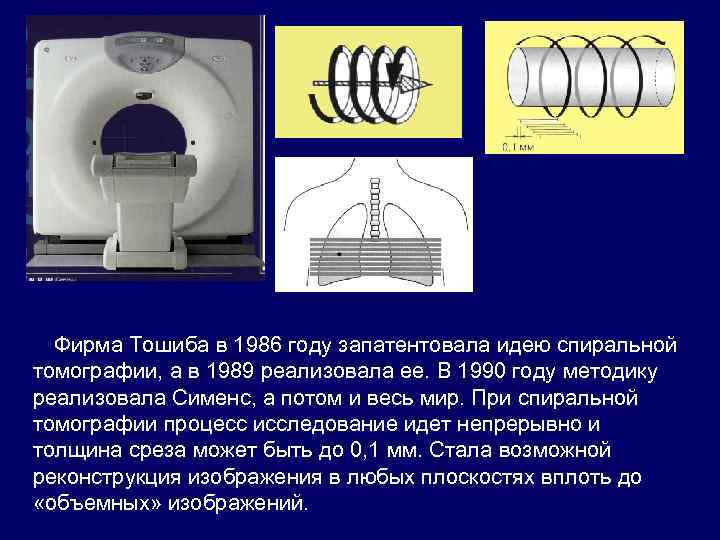

Фирма Тошиба в 1986 году запатентовала идею спиральной томографии, а в 1989 реализовала ее. В 1990 году методику реализовала Сименс, а потом и весь мир. При спиральной томографии процесс исследование идет непрерывно и толщина среза может быть до 0, 1 мм. Стала возможной реконструкция изображения в любых плоскостях вплоть до «объемных» изображений.